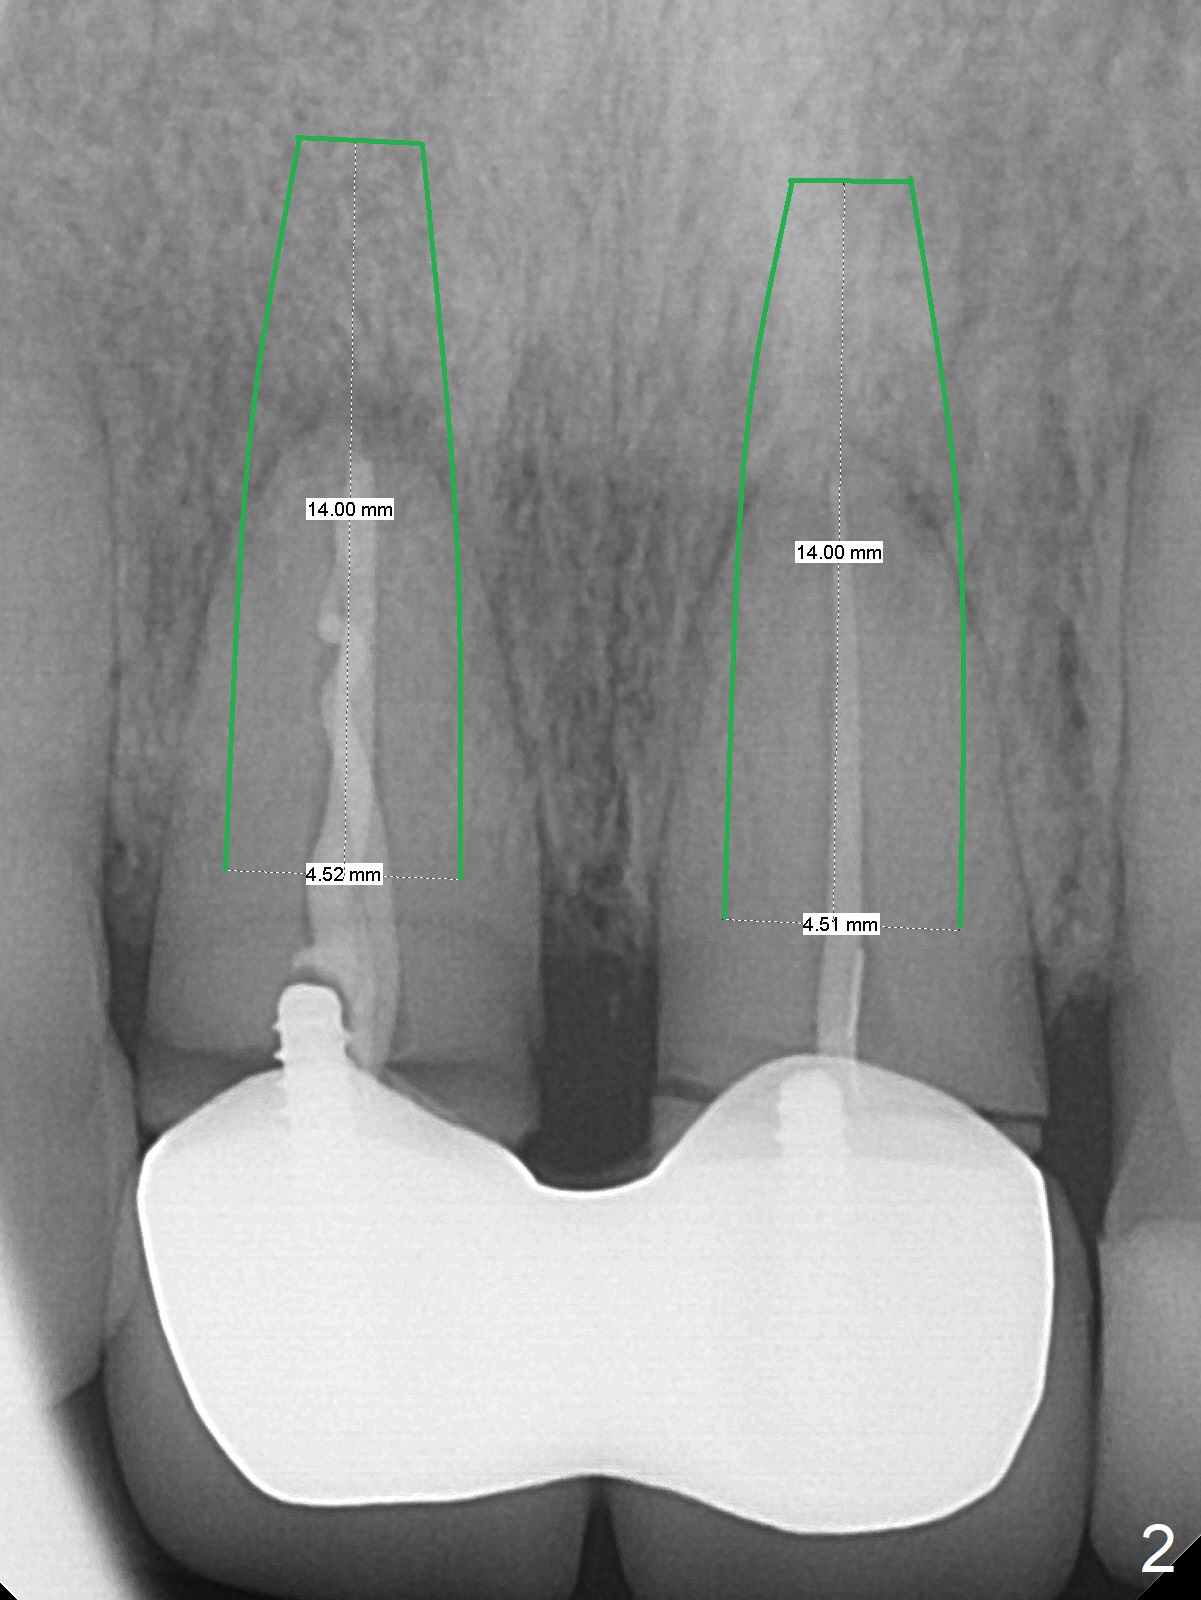

A 36-year-old woman fractures the teeth 8 and 9 while the implant at #3 is healing (Fig.1 arrowheads). It appears that the teeth are wide enough to accept 4.5x14 mm implants (Fig.2).